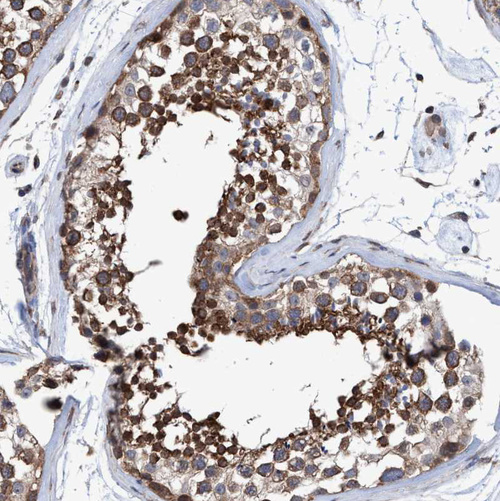

Immunohistochemical staining of human Tonsil shows strong cytoplasmic positivity in germinal center cells.